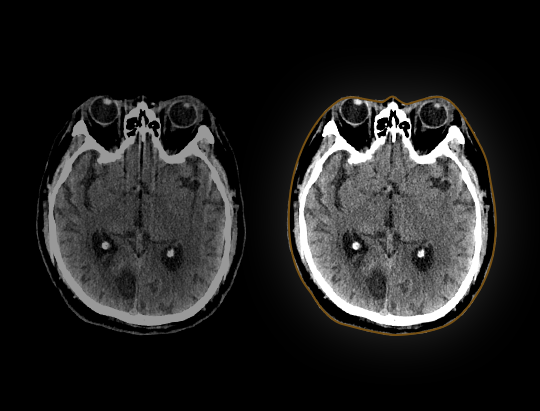

Algoritm de corecție a mișcărilor capului bazat pe inteligență artificială, care elimină artefactele de mișcare și dezvăluie acuratețea reală a imaginilor.

Perfuzie cerebrală dinamică 180 mm

Tehnica de perfuzie dinamică oferă un câmp de scanare mai larg decât acoperirea detectorului și furnizează informații funcționale complete despre creier, cu un timp de ciclu de până la 2 secunde.

Post-procesare automată*

Prin utilizarea funcției automate de eliminare a oaselor, imaginile CTA pot fi obținute rapid și precis. În plus, software-ul de analiză CTP oferă o gamă variată de parametri funcționali – CBV, CBF, TTP, MTT și Tmax – care îmbunătățesc precizia diagnosticării în cazul accidentului vascular cerebral ischemic.